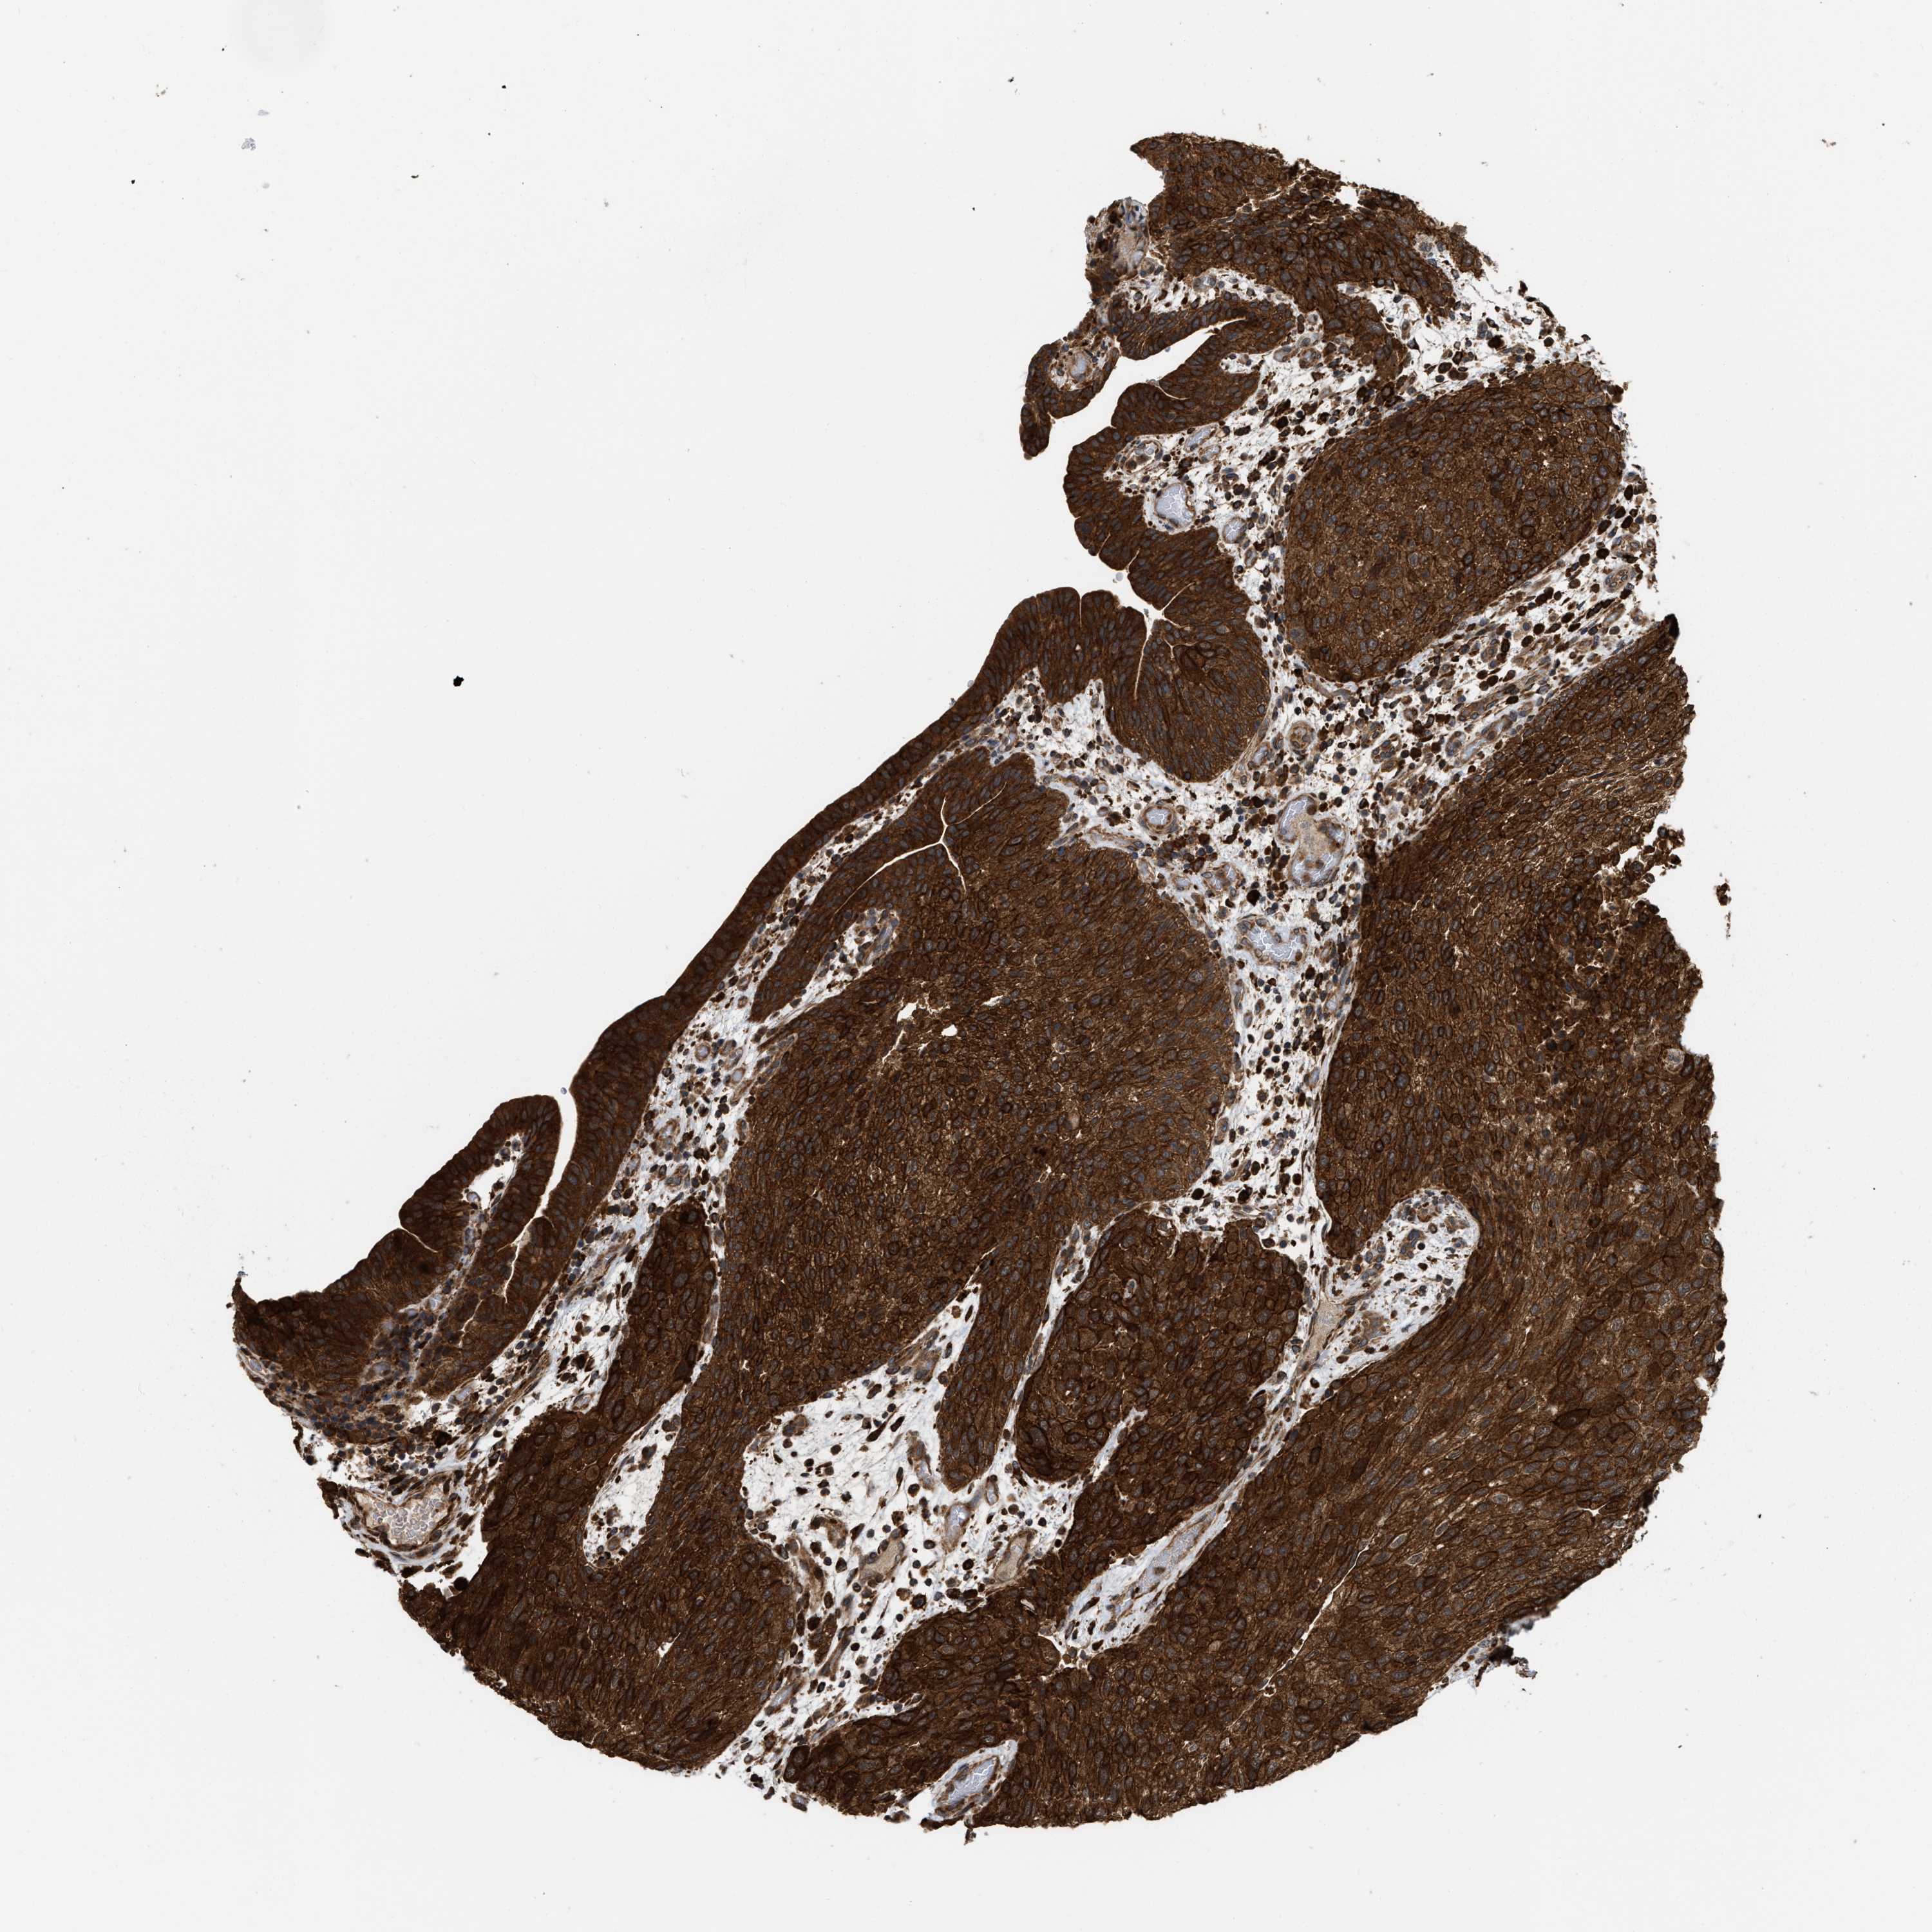

UROTHELIAL CANCER - Protein expressioni

A mouse-over function shows sample information and annotation data. Click on an image to view it in a full screen mode. Samples can be filtered based on level of antibody staining by selecting one or several of the following categories: high, medium, low and not detected. The assay and annotation is described here.

Note that samples used for immunohistochemistry by the Human Protein Atlas do not correspond to samples in the TCGA dataset.

Antibody stainingi

Antibody staining in the annotated cell types in the current human tissue is reported as not detected, low, medium, or high, based on conventional immunohistochemistry profiling in selected tissues. This score is based on the combination of the staining intensity and fraction of stained cells.

Each image is clickable and will lead to virtual microscopy that enables deeper exploration of all samples and also displays staining intensity scores, fraction scores and subcellular localization as well as patient and tissue information for each sample.

Antibody HPA019515

Staining

High

Medium

Low

Not detected

Intensity

Strong

Moderate

Weak

Negative

Quantity

>75%

75%-25%

<25%

None

Location

Nuclear

Cytoplasmic/membranous

Cytoplasmic/membranous,nuclear

Urothelial carcinoma, Low grade

Urothelial carcinoma, High grade